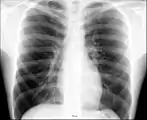

Anatomie radiographique d'une poitrine humaine.